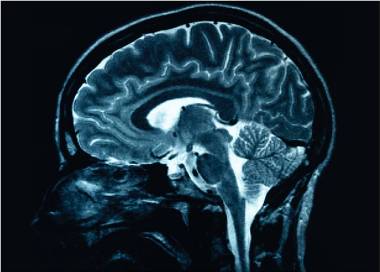

Poluarea aerului poate contribui în mod direct la apariţia bolii Alzheimer, arată un studiu de specialitate

Persoanele cele mai expuse la poluarea atmosferică pot avea un risc mai mare de a dezvolta boala Alzheimer, o asociere care este mai semnificativă în cazul celor care au suferit un accident vascular cerebral, ceea ce sugerează că această categorie poate fi mai vulnerabilă, transmite agenţia de știri EFE, citată de Agerpres. Expunerea la poluarea […]